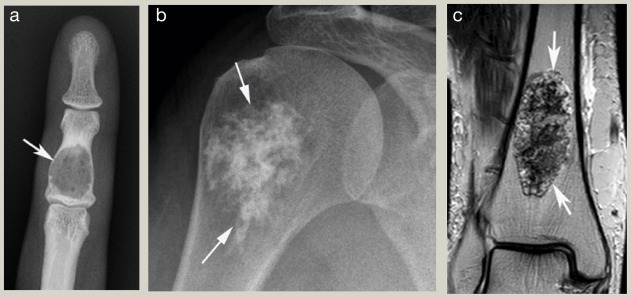

- عکس رادیولوژی یا اشعه ایکس

اولین روش برای بررسی استخوان و مشاهده تغییرات ناشی از تومور است. این تصاویر می توانند نشان دهند که آیا استخوان ضعیف یا تخریب شده است یا خیر. - سی تی اسکن (CT scan)

این روش جزئیات بیشتری از ساختار استخوان نشان می دهد و به پزشک کمک می کند اندازه و محل دقیق تومور را بررسی کند. - ام آر آی (MRI)

ام آر آی یکی از بهترین روش ها برای بررسی بافت های نرم اطراف استخوان و میزان گسترش تومور است. - اسکن استخوانی (Bone Scan)

تشخیص دقیق تومور با استفاده از روش های پیشرفته تصویربرداری مانند رادیولوژی، سی تی اسکن و ام آر آی انجام می شود. نمونه برداری و بررسی بافت از اهمیت بالایی برای تعیین خوش خیم یا بدخیم بودن تومور برخوردار است.